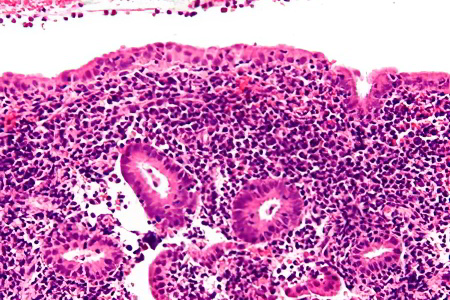

Изменения в матке включают:

• Расширение кровеносных сосудов, питающих орган.

• Увеличение толщины эндометрия.

• Появление гнойного налета на слизистых оболочках, что приводит к отмиранию клеток.

• Пережатие желез матки, что вызывает активную выработку воспалительного экссудата. В результате у женщины значительно увеличивается количество влагалищных выделений.

Хронический эндометрит развивается медленно. Слизистая оболочка матки постепенно разрушается и заменяется соединительной тканью, что приводит к утрате её естественных функций.

• Изменения в структуре эндометрия с образованием глубоких очагов поражения.